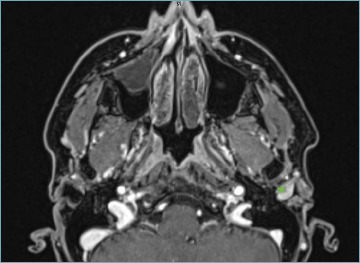

Abstract Image